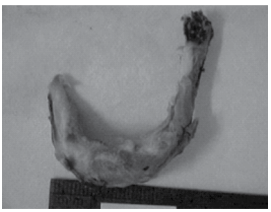

A figura seguinte representa osso hioide fraturado em vítima de suicídio por enforcamento.

Além do osso hioide, outras estruturas comumente passíveis de lesão nas asfixias por contricção do pescoço são:

Além do osso hioide, outras estruturas comumente passíveis de lesão nas asfixias por contricção do pescoço são: